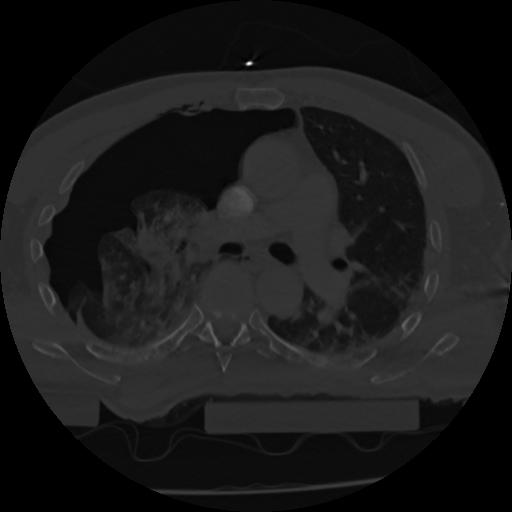

22 ANGIO,CE,Vol,0.5,ANGIO,,